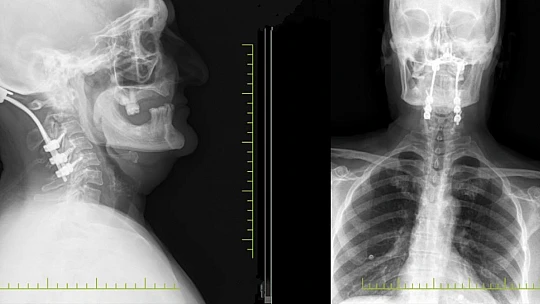

Ukrayna’da devam eden savaşta ülkede mahsur kalan Ahıska Türkleri, tahliye edilerek Elazığ’a getirilmiş ve Aşağıdemirtaş Geçici Konaklama Merkezine yerleştirilmişti. Burada yaşayan bir vatandaş, desteksiz yürüyememe ve boyun ağrıları şikayetleri ile Fethi Sekin Şehir Hastanesi Beyin Cerrahi Kliniğine müracaat etti. Hastanede ayrıntılı muayene ve tetkiklerde hastanın boynunda tümör olduğu saptandı. Beyin ve sinir cerrahisi kliniğinde başarıyla ameliyatı yapılan hasta, sağlığına kavuştu.

Beyin ve Sinir Cerrahisi Uzmanı Opr. Dr. Fatih Demir, “Boynundaki tümörün etkisiyle omurgada kırık ve açılanma gelişen hastamız ayakta durmakta güçlük çekiyor ve desteksiz yürüyemiyordu. Yaptığımız detaylı muayene ve tetkiklerle boynundaki tümörün hastadaki şikayetlere sebep olduğunu saptadık. Hastamızı ameliyat ederek baş ile boyun omurlarını sabitledik ve omuriliğe bası yapan tümörünü çıkardık. Başvurduğunda ayakta durmakta güçlük çeken ve desteksiz yürüyemeyen hastamızı yürüyerek taburcu ettik" dedi.